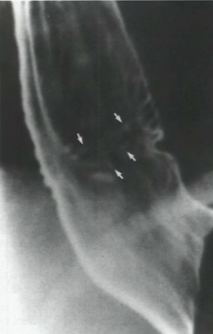

What is your diagnosis?

Note the large thickened areas at the base of the tongue, indicating lymphoid hyperplasia.